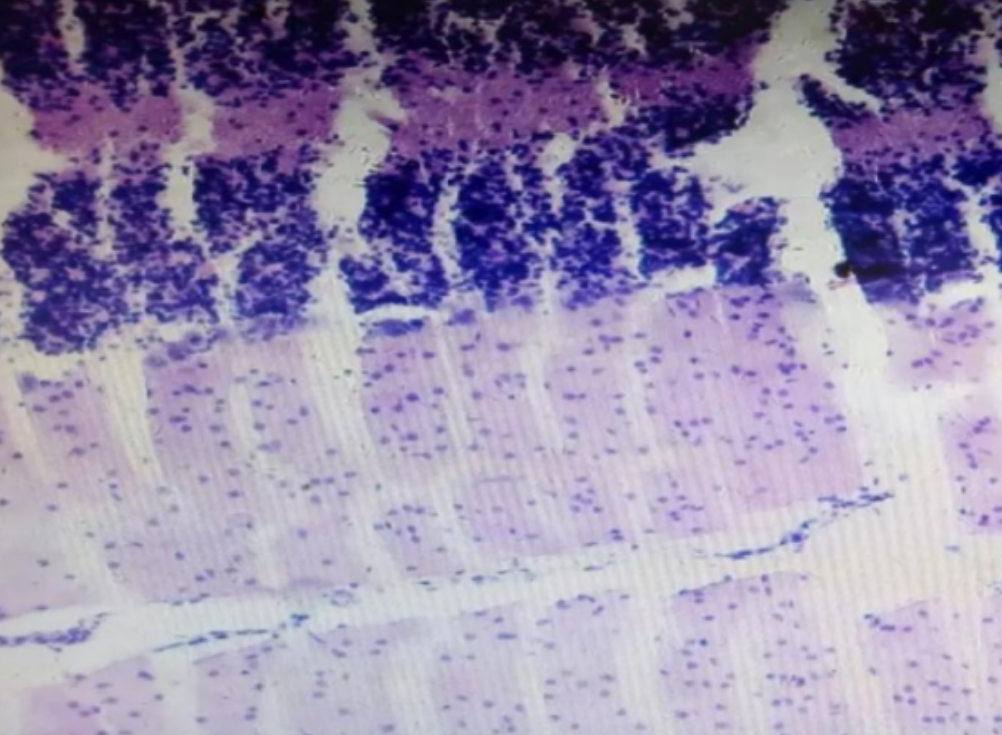

形成原因:切片经梯度乙醇处理后没有完全脱水,导致二甲苯透明、中性树胶封固后残留大量水分。 解决方法:首先移去盖玻片,用二甲苯溶解封固剂如中性树胶,再将切片置入无水乙醇内,待切片重新脱水完全后,用二甲苯透明处理,中性树胶封固。要注意所有用于脱水和透明的液体,在使用一定时间后,应及时更换。 二、细胞核呈红、棕色 形成原因:苏木精染色液过度氧化,切片在苏木精染液染色后返蓝不足。 解决方法:每次染色之前检查苏木精染色液的染色能力,发现苏木精染色液氧化过度应及时更换。此外,切片经苏木精染色后,要给切片以足够的蓝化时间,蓝化过程可用流水、温水、弱碱性溶液(如稀氨水或0.2%碳酸氢钠)等处理。 三、切片在脱蜡后出现大片白色斑点 形成原因:由于烤(烘)片温度太低,切片上的组织蜡膜在脱蜡前没有充分烤(烘)融化。或是因为切片在二甲苯液中停留时间不足,或二甲苯使用过久,造成的脱蜡不彻底。 解决方法:若是由于切片烤(烘)温度低所致,可以先用二甲苯去除切片上的封固胶,然后重新用二甲苯脱去切片上的石蜡,再进行后续染色。若是由于切片在脱蜡的二甲苯中停留时间不足或脱蜡二甲苯使用过久浓度不足所致,则需将切片退回到二甲苯中,停留较长时间,或更换二甲苯液体重新脱蜡,再入乙醇重新脱二甲苯,入0.5%盐酸水溶液褪色后,重新HE染色。 四、细胞核苍白暗淡,即苏木精染色太淡 形成原因:切片在苏木精染色液停留时间太短;苏木精染色液过度氧化,失去染色能力,不能再继续使用;分化步骤处理时间过长;固定不及时。此外值得注意的是,若骨组织细胞核暗淡,大多是脱钙过度造成的。 解决方法:切片重新染色。如果组织在酸性固定液(如Zenker、Bouin)或非中性缓冲甲醛液固定时间过长,细胞核染色能力将减弱,需增加其在苏木精染色液的时间,或用一些方法增加组织的嗜碱性,以改善细胞核的着色。例如,上述组织玻片可以使用Weigert铁苏木精染色液。如果组织是用Zenker液固定的,可将切片脱蜡后放在5%碳酸氢钠溶液3~4h,流水冲洗5min后染色。如果组织是用Bouin液固定的,可将切片脱蜡后放在5%碳酸锂1h,流水冲洗10min后染色。 五、细胞核过染,苏木精染液占据了细胞质 形成原因:玻片在苏木精染色液停留时间过长,或是切片太厚、分化步骤时间太短。 解决方法:如果不是因为切片太厚(用显微镜仔细上下微调,只有一二层细胞核层次),就需将切片进行脱色、漂白、重新染色,适当调整染色和分化时间。但如果确定是由于切片太厚导致的细胞核过染,则需要重新切片。 六、伊红着色淡 形成原因:可能是伊红染液pH值大于5,也可能是蓝化液残留过多,切片太薄,或是切片经伊红染色后在乙醇脱水时间过长。 解决方法:检查伊红染液pH值,必要的话,用乙酸将其调节在4.6~5.0之间,从而使伊红染色色彩艳丽。此外,确保每次蓝化步骤完成后,使用的弱碱性溶液被充分洗去,玻片上没有残留的弱碱性溶液。最后,检查切片的厚度,且脱水时不要让切片在低浓度乙醇中停留时间过长,因为含水多的低浓度乙醇会将切片伊红的颜色分化掉。 七、细胞质过染、分色不足 形成原因:伊红染色液浓度太高,特别是存在焰红燃料、四溴四氯荧光素钠。切片在伊红染色时间过长,或是切片在伊红染色后经乙醇脱水步骤时时间太短,而使乙醇分化伊红的作用不能产生,都能够使细胞质过染。 解决方法:适当稀释伊红染色液,减少伊红染色时间,或使切片在乙醇脱水等步骤时,停留时间相对均匀。同样,也要检查切片的厚度是否合适。 八、切片中出现蓝黑色沉淀物 形成原因:苏木精染色液中的金属膜黏附在玻片上。 解决方法:染色前仔细过滤苏木精染色液,建议使用半氧化苏木精染色液,如Gill苏木精染色液,可以避免过多的金属膜产生。 九、光镜下切片某些区域难以聚焦 形成原因:盖玻片上可能有封固切片的封固剂。 解决方法:移去盖玻片,重新用干净的盖玻片封片。检查切片封片方法,是人工手工封法,还是机器自动封法,如有问题及时调整。 十、封固剂从盖玻片与载玻片之间的缝隙回缩 形成原因:盖玻片弯曲或不平整,或是封固剂含二甲苯过多,稀释过度。 解决方法:移去盖玻片,重新找一张盖玻片,用干净的封固剂封片。如用手工封片法,保证在封固结束时,封固剂容器盖子为紧闭状态。且尽量使用小的容器盛装封固剂,一旦封固剂太黏稠,就可以选择废弃。 十一、细胞核呈灰蓝状态 形成原因:可能由于组织处理温度过高、过热,在液体石蜡中停留的时间过长。或是固定时间太短后,直接在高浓度的乙醇中进行了脱水处理。 解决方法:理论上来说,仅在组织浸蜡步骤才进行加热,组织不能在热蜡液中停留太久。如果由于某些原因不能进行下一步包埋处理,可将组织连同塑料包埋盒一并放置在室温空气中,冷却凝固,以备包埋。待需要包埋时再重新加温直至石蜡融化即可。组织在处理前必须确保固定良好,脱水最好能从低浓度的乙醇开始。 十二、类色素的点状结晶和黑色光滑细胞核 形成原因:这种裸核改变是因为切片封片前放置在空气中的时间太长,以至于二甲苯挥发,切片干燥。 解决方法:移去组织切片上的盖玻片和封固剂,重新处理。将切片水洗数分钟,然后重新脱水、透明、封固。封片过程中要保持组织切片的轻度湿润,尽量不要让其干燥。 十三、染色过淡或过浓 解决方法:如果染色过淡,可以增加染色剂的浓度、延长染色时间或更换新鲜的染色剂;如果染色过浓,则应减少染色剂的浓度或缩短染色时间。 十四、切片出现叠加褶皱 形成原因:新购买的玻片洁净度不够、用镊子撑开切片时操作不够熟练未能平整伸展,或玻片表面有油脂,切片粘贴不牢。另外,烤片时间不足、烤片温度过低或切片过厚造成切片脱落,都会造成重叠或有皱褶的情况。 解决方法:新购买的玻片最好能用硫酸清洁液浸泡一晚,然后流水冲洗干净。在适宜的温度下烤片时间宁长勿短,保证有充足的烤片时间和温度。另外,切片刀要锋利,才能切出厚薄适宜的切片,保证切片不会因为过厚而脱落。 十五、组织残缺不全或有刮划痕迹 形成原因:组织残缺不全是由于切片时修整蜡块时深度不够、组织没有全部暴露于切面。切片的刮划痕迹是由于切片刀的刀锋有缺口、包埋的组织有异物,或是钙化组织、骨组织及包埋石蜡有沙粒造成的。 解决方法:修整蜡块时保证组织块全部暴露于切面,切片时保证切片刀的锋利没刀口。同时在组织取材时去除手术异物和钙化组织。最后,骨组织要完全脱钙,这样可以保证切片的完整和平整美观。 *注:由于实验中导致结果出现误差的原因多种多样,以上内容仅供参考,具体根据实际情况进行判断。